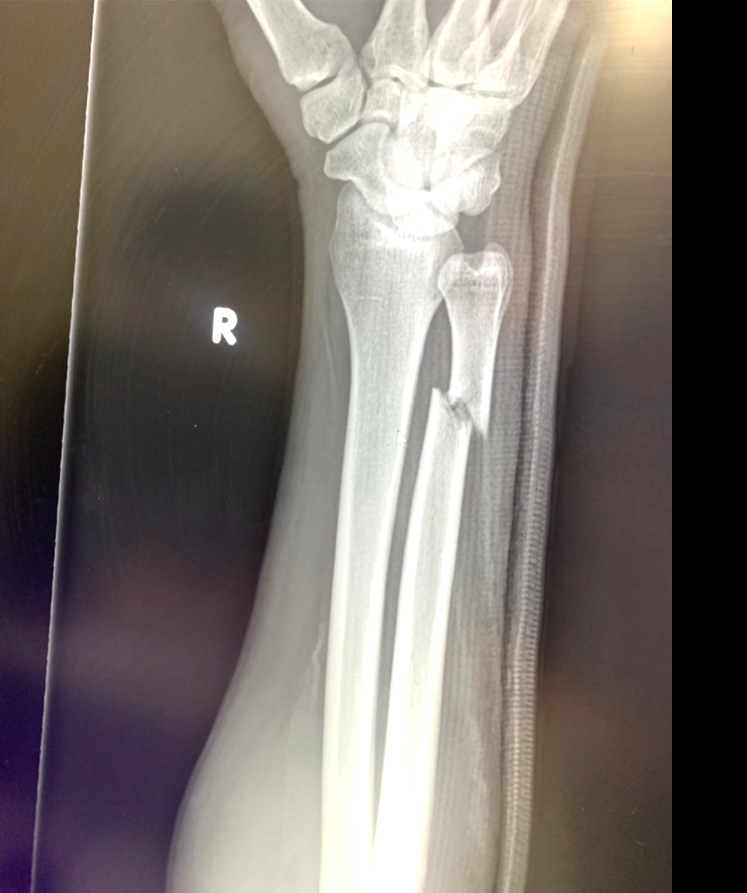

ブディオの右腕骨折のレントゲン写真(ダニロ・ザノリニのFacebookより)